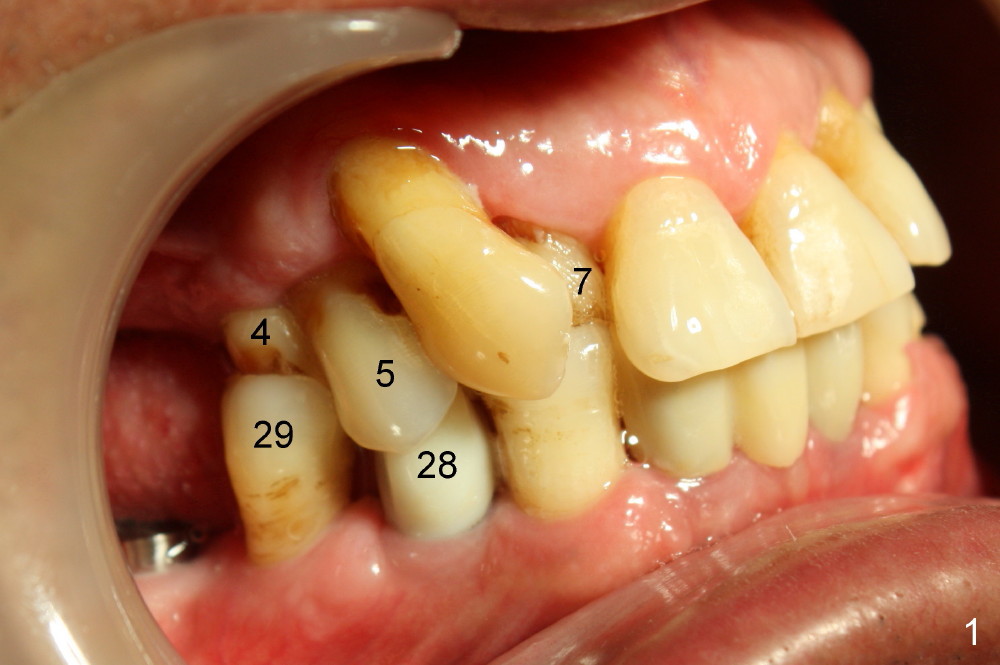

The patient returns for orthodontic treatment 7-8 months post implantation at the sites of #3, 20, 21, and 30 (Fig.4,6,7). He is willing to let the tooth #5 be extracted if necessary, since it has mobility. The tooth is only the functioning posterior tooth in his mouth (Fig.1). It must have occlusal overloading, particularly opposing the implant tooth #28 (Fig.1,7). Multiple implants and ortho treatment appear to be needed.